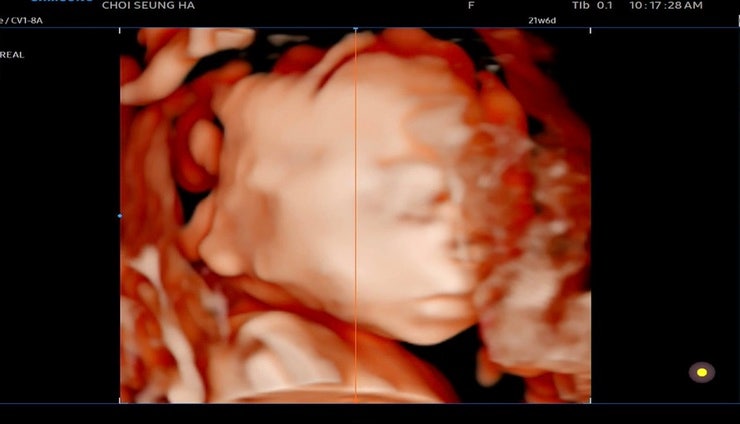

찰떡이❤️21주6일 정밀초음파

21주6일 정밀초음파 드뎌 정밀초음파날.. 당연히 아무 이상없이 모든게 정상100점 받을줄 알았다.. 모든것...